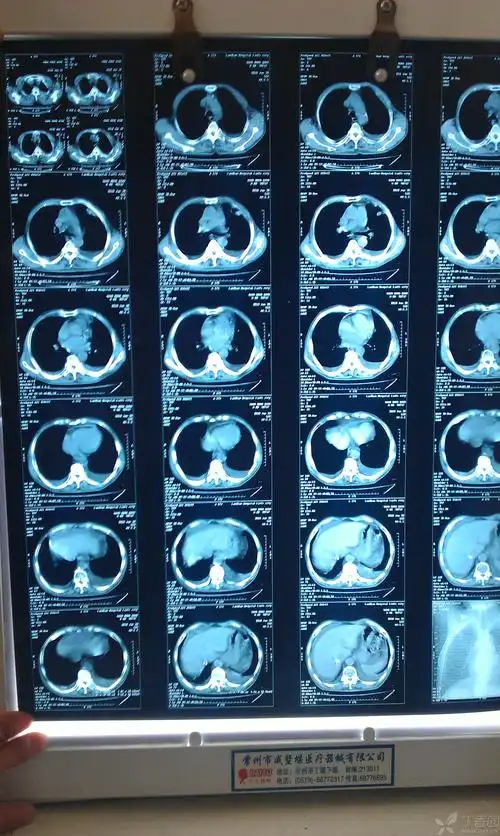

早期肺癌ct图

【读片】肺癌? [病例帖]

胸部x射线 ct增强片 帮帮忙看一下 是肺癌吗?